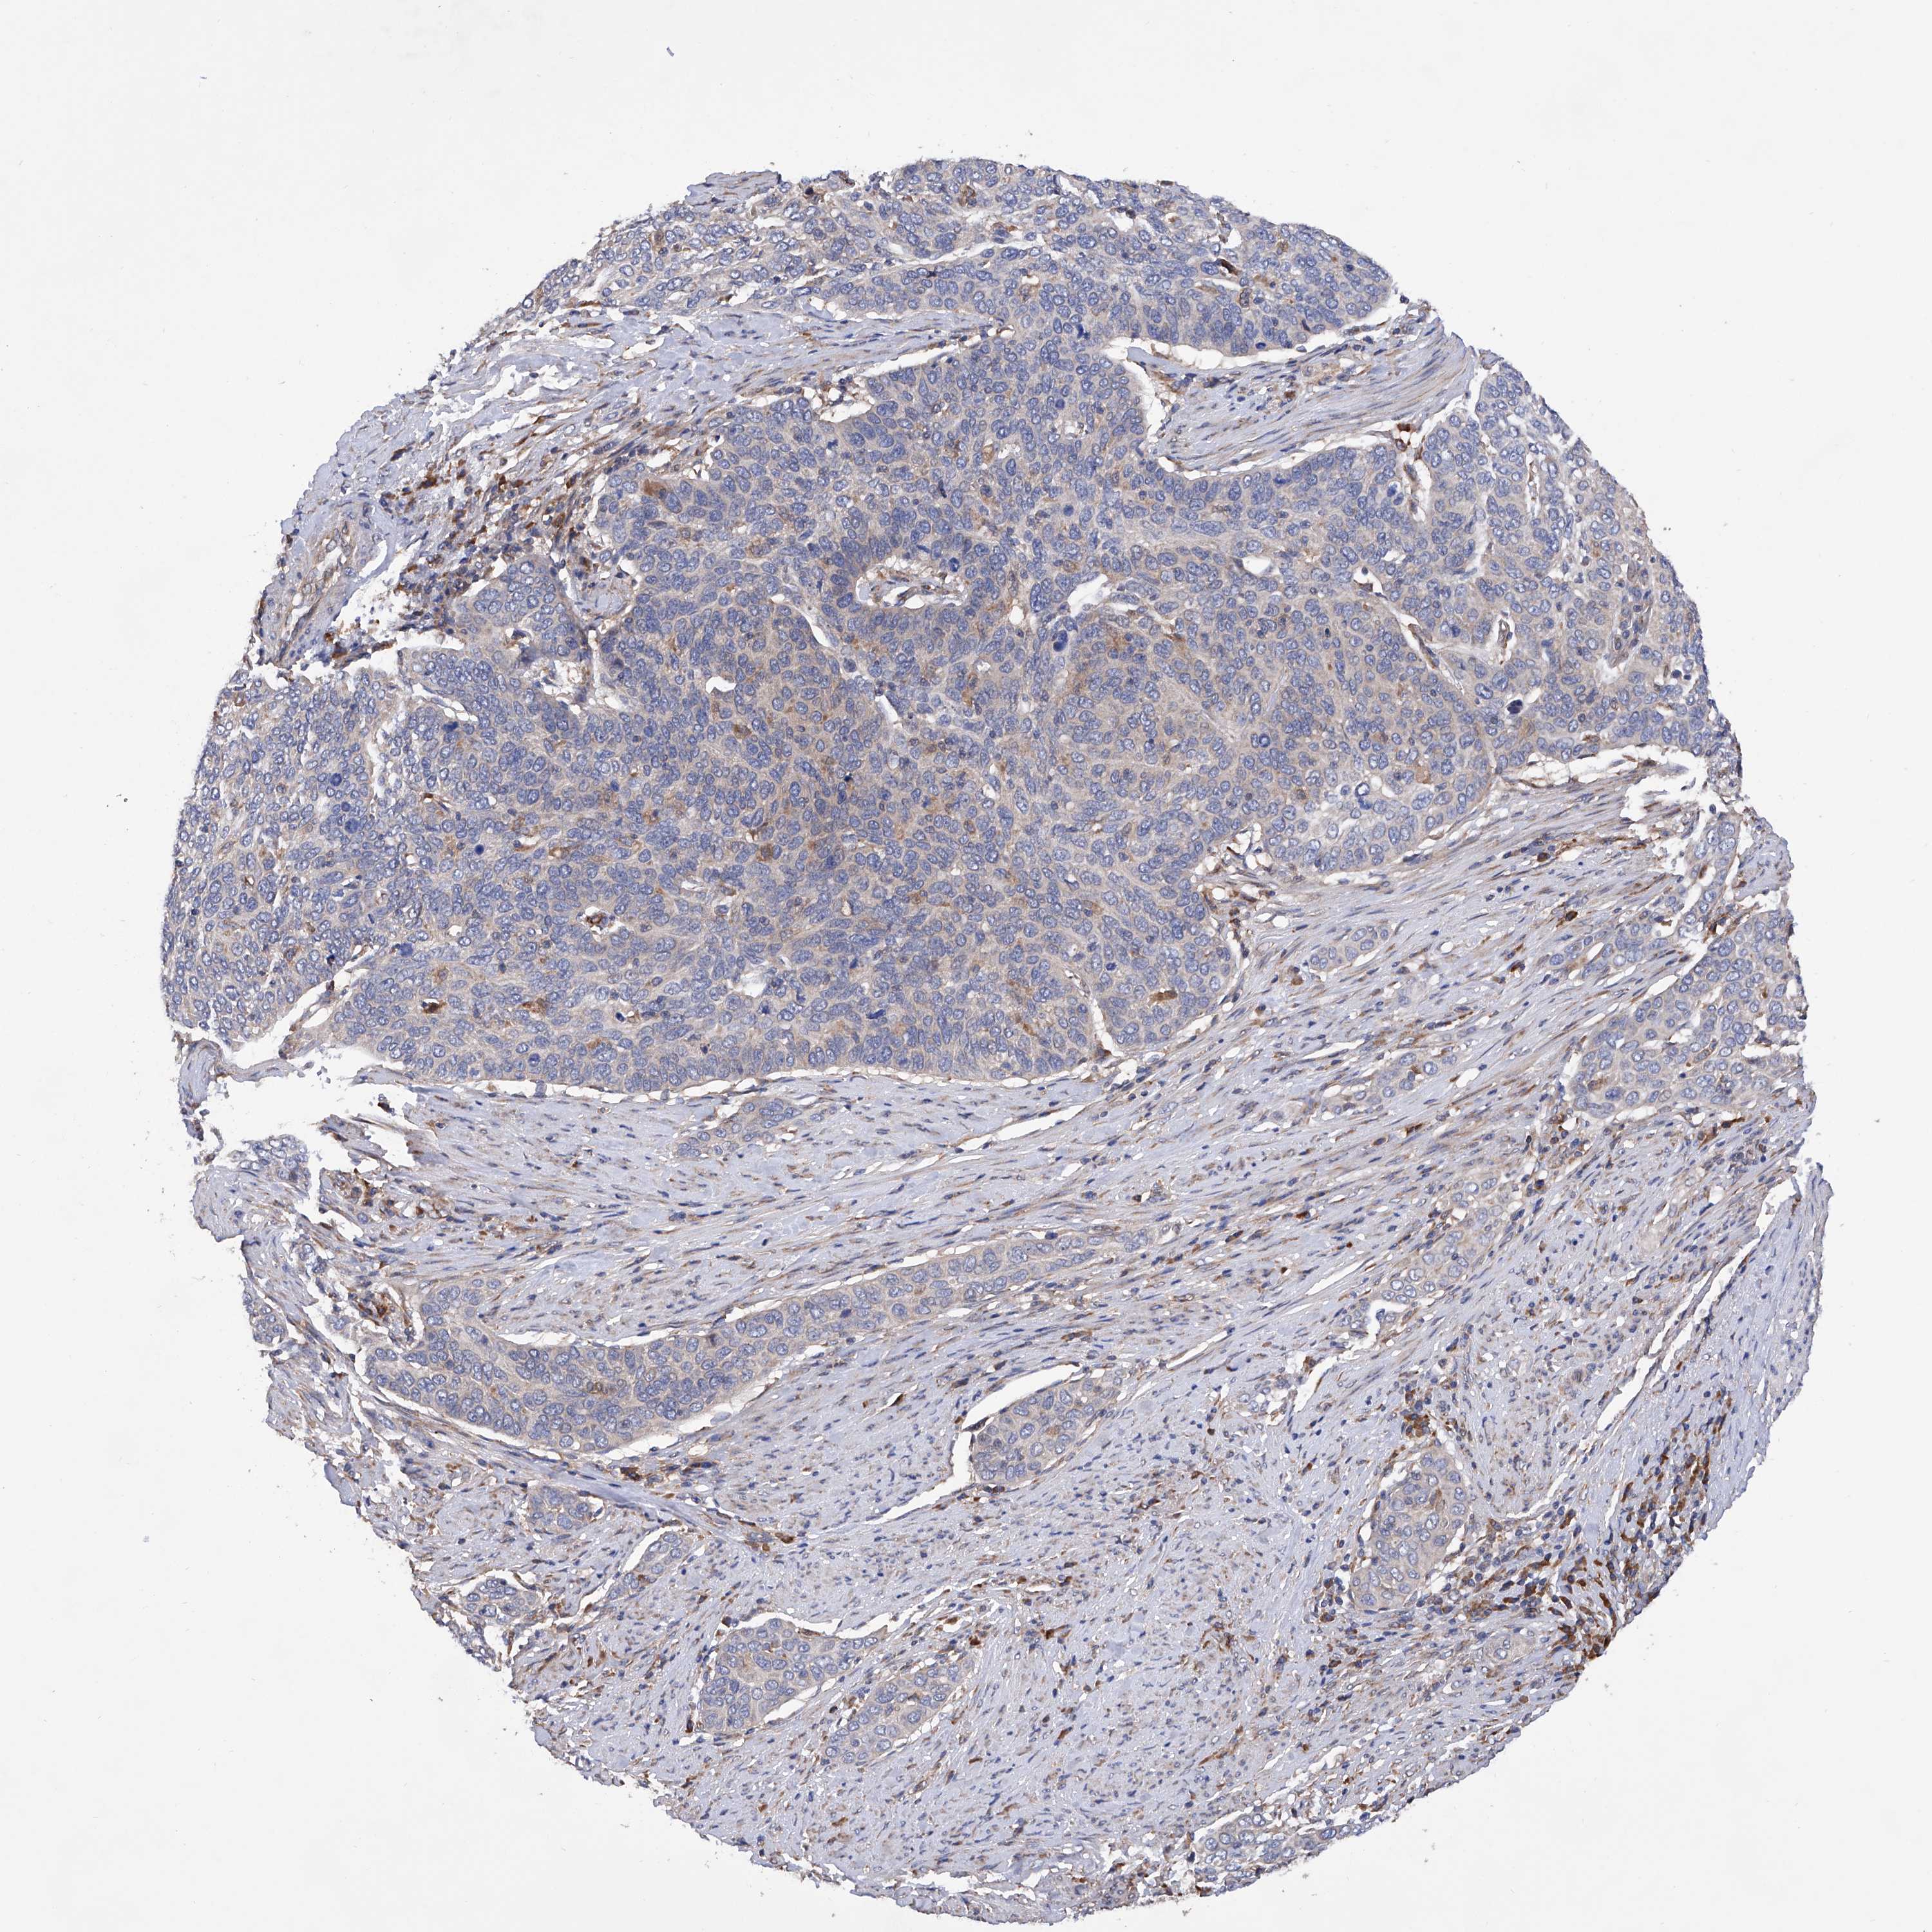

CERVICAL CANCER - Protein expressioni

A mouse-over function shows sample information and annotation data. Click on an image to view it in a full screen mode. Samples can be filtered based on level of antibody staining by selecting one or several of the following categories: high, medium, low and not detected. The assay and annotation is described here.

Note that samples used for immunohistochemistry by the Human Protein Atlas do not correspond to samples in the TCGA dataset.

Antibody stainingi

Antibody staining in the annotated cell types in the current human tissue is reported as not detected, low, medium, or high, based on conventional immunohistochemistry profiling in selected tissues. This score is based on the combination of the staining intensity and fraction of stained cells.

Each image is clickable and will lead to virtual microscopy that enables deeper exploration of all samples and also displays staining intensity scores, fraction scores and subcellular localization as well as patient and tissue information for each sample.

Antibody HPA028803

Staining

High

Medium

Low

Not detected

Intensity

Strong

Moderate

Weak

Negative

Quantity

>75%

75%-25%

<25%

None

Location

Nuclear

Cytoplasmic/membranous

Cytoplasmic/membranous,nuclear

Adenocarcinoma, NOS